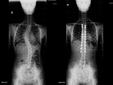

Skolyoz, omurganın yana doğru eğilmesiyle karakterize edilen bir durumdur. Genellikle ergenlik döneminde ortaya çıkar ve çeşitli nedenlere bağlı olarak gelişir. Bu yazıda skolyozun nedenleri, türleri ve etkili tedavi yöntemleri hakkında bilgi verilecektir. Erken tanı ve uygun tedavi, hastalığın yönetiminde büyük önem taşımaktadır.

Skolyoz Nasıldır, Hangi Yöntemler Etkilidir?Skolyoz, omurganın yana doğru eğilmesi ile karakterize edilen bir durumdur. Genellikle ergenlik döneminde ortaya çıkar ve çeşitli nedenlerden kaynaklanabilir. Skolyozun tedavisi, eğilimin şiddetine, hastanın yaşına ve genel sağlık durumuna bağlı olarak değişiklik gösterir. Bu makalede, skolyozun düzeltilmesi için etkili yöntemler ele alınacaktır. Skolyozun Nedenleri ve TürleriSkolyoz, genetik faktörler, doğumsal anomaliler, sinir kas hastalıkları veya bilinmeyen nedenler gibi çeşitli etkenlerden kaynaklanabilir. Skolyoz türleri arasında en yaygın olanları şunlardır:

Her bir tür, farklı tedavi yaklaşımları gerektirebilir. İdiyopatik skolyoz, genellikle ergenlik döneminde ortaya çıkar ve tedavi edilmediğinde ciddi sorunlara yol açabilir. Skolyozun TanısıSkolyozun tanısı genellikle fizik muayene ve görüntüleme yöntemleri ile konur. Doktor, hastanın duruşunu değerlendirir ve gerekirse röntgen çekimi yapar. Röntgen, omurganın eğilimini ve açılarını belirlemeye yardımcı olur. Skolyoz Tedavi YöntemleriSkolyoz tedavisinde kullanılan başlıca yöntemler şunlardır: